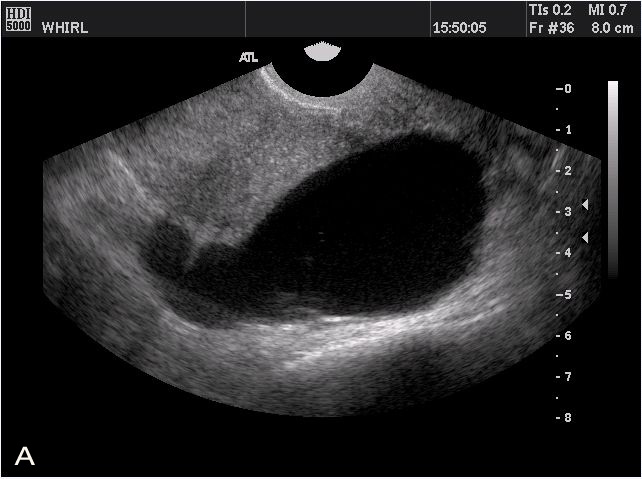

A case of hydrosalpinx associated with the menstrual cycle Yutaka Osuga, M.D., Ph.D., Kaori Koga, M.D., Hydrosalpinx, ultrasound, endometriosis, menstrual cycle, Sequential change of ultrasonographic images of the left fallopian tube in a representative menstrual cycle. (A) ... Content Retrieval